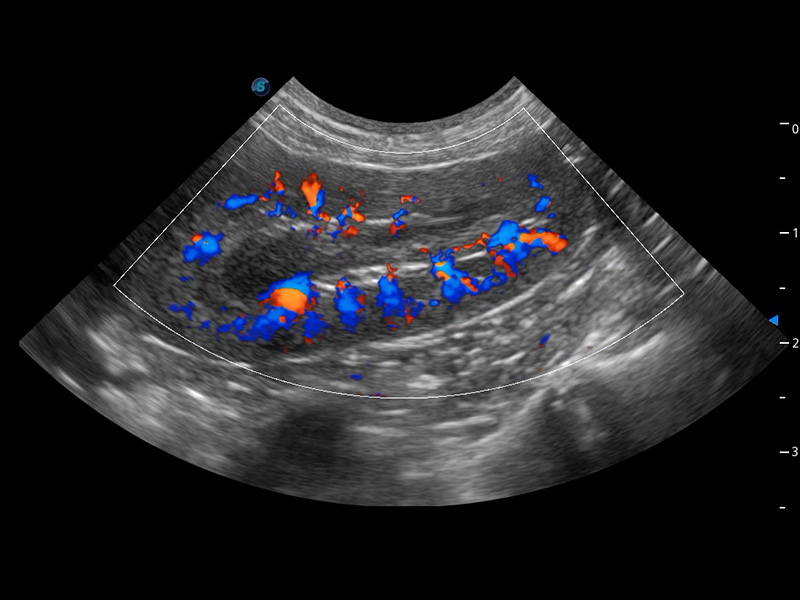

ProPet 60 作为一款高端台式动物超声设备,为动物医生的日常诊断提供了一系列贴合动物临床需求、解决临床实际问题的高级成像功能。凭借全系列高清探头,满足医生对腹部、心脏、生殖、浅表、肌骨等成像的所有需求,切实帮助您提升检查效率,提高诊断信心。

ProPet 60 尊享版

兽用彩色多普勒超声诊断系统